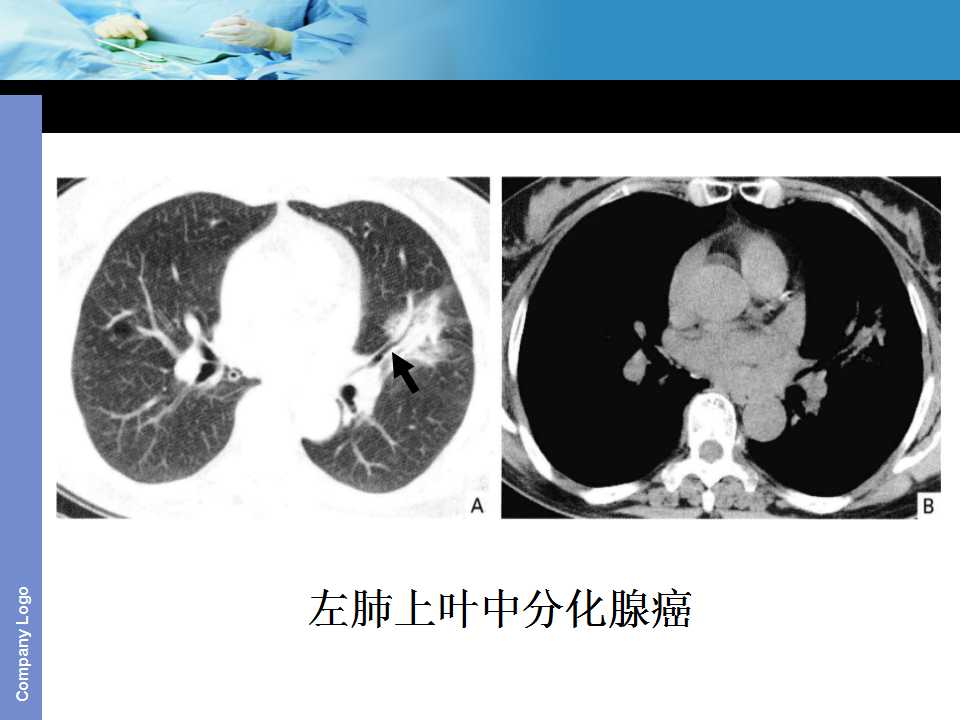

肺癌影像诊断